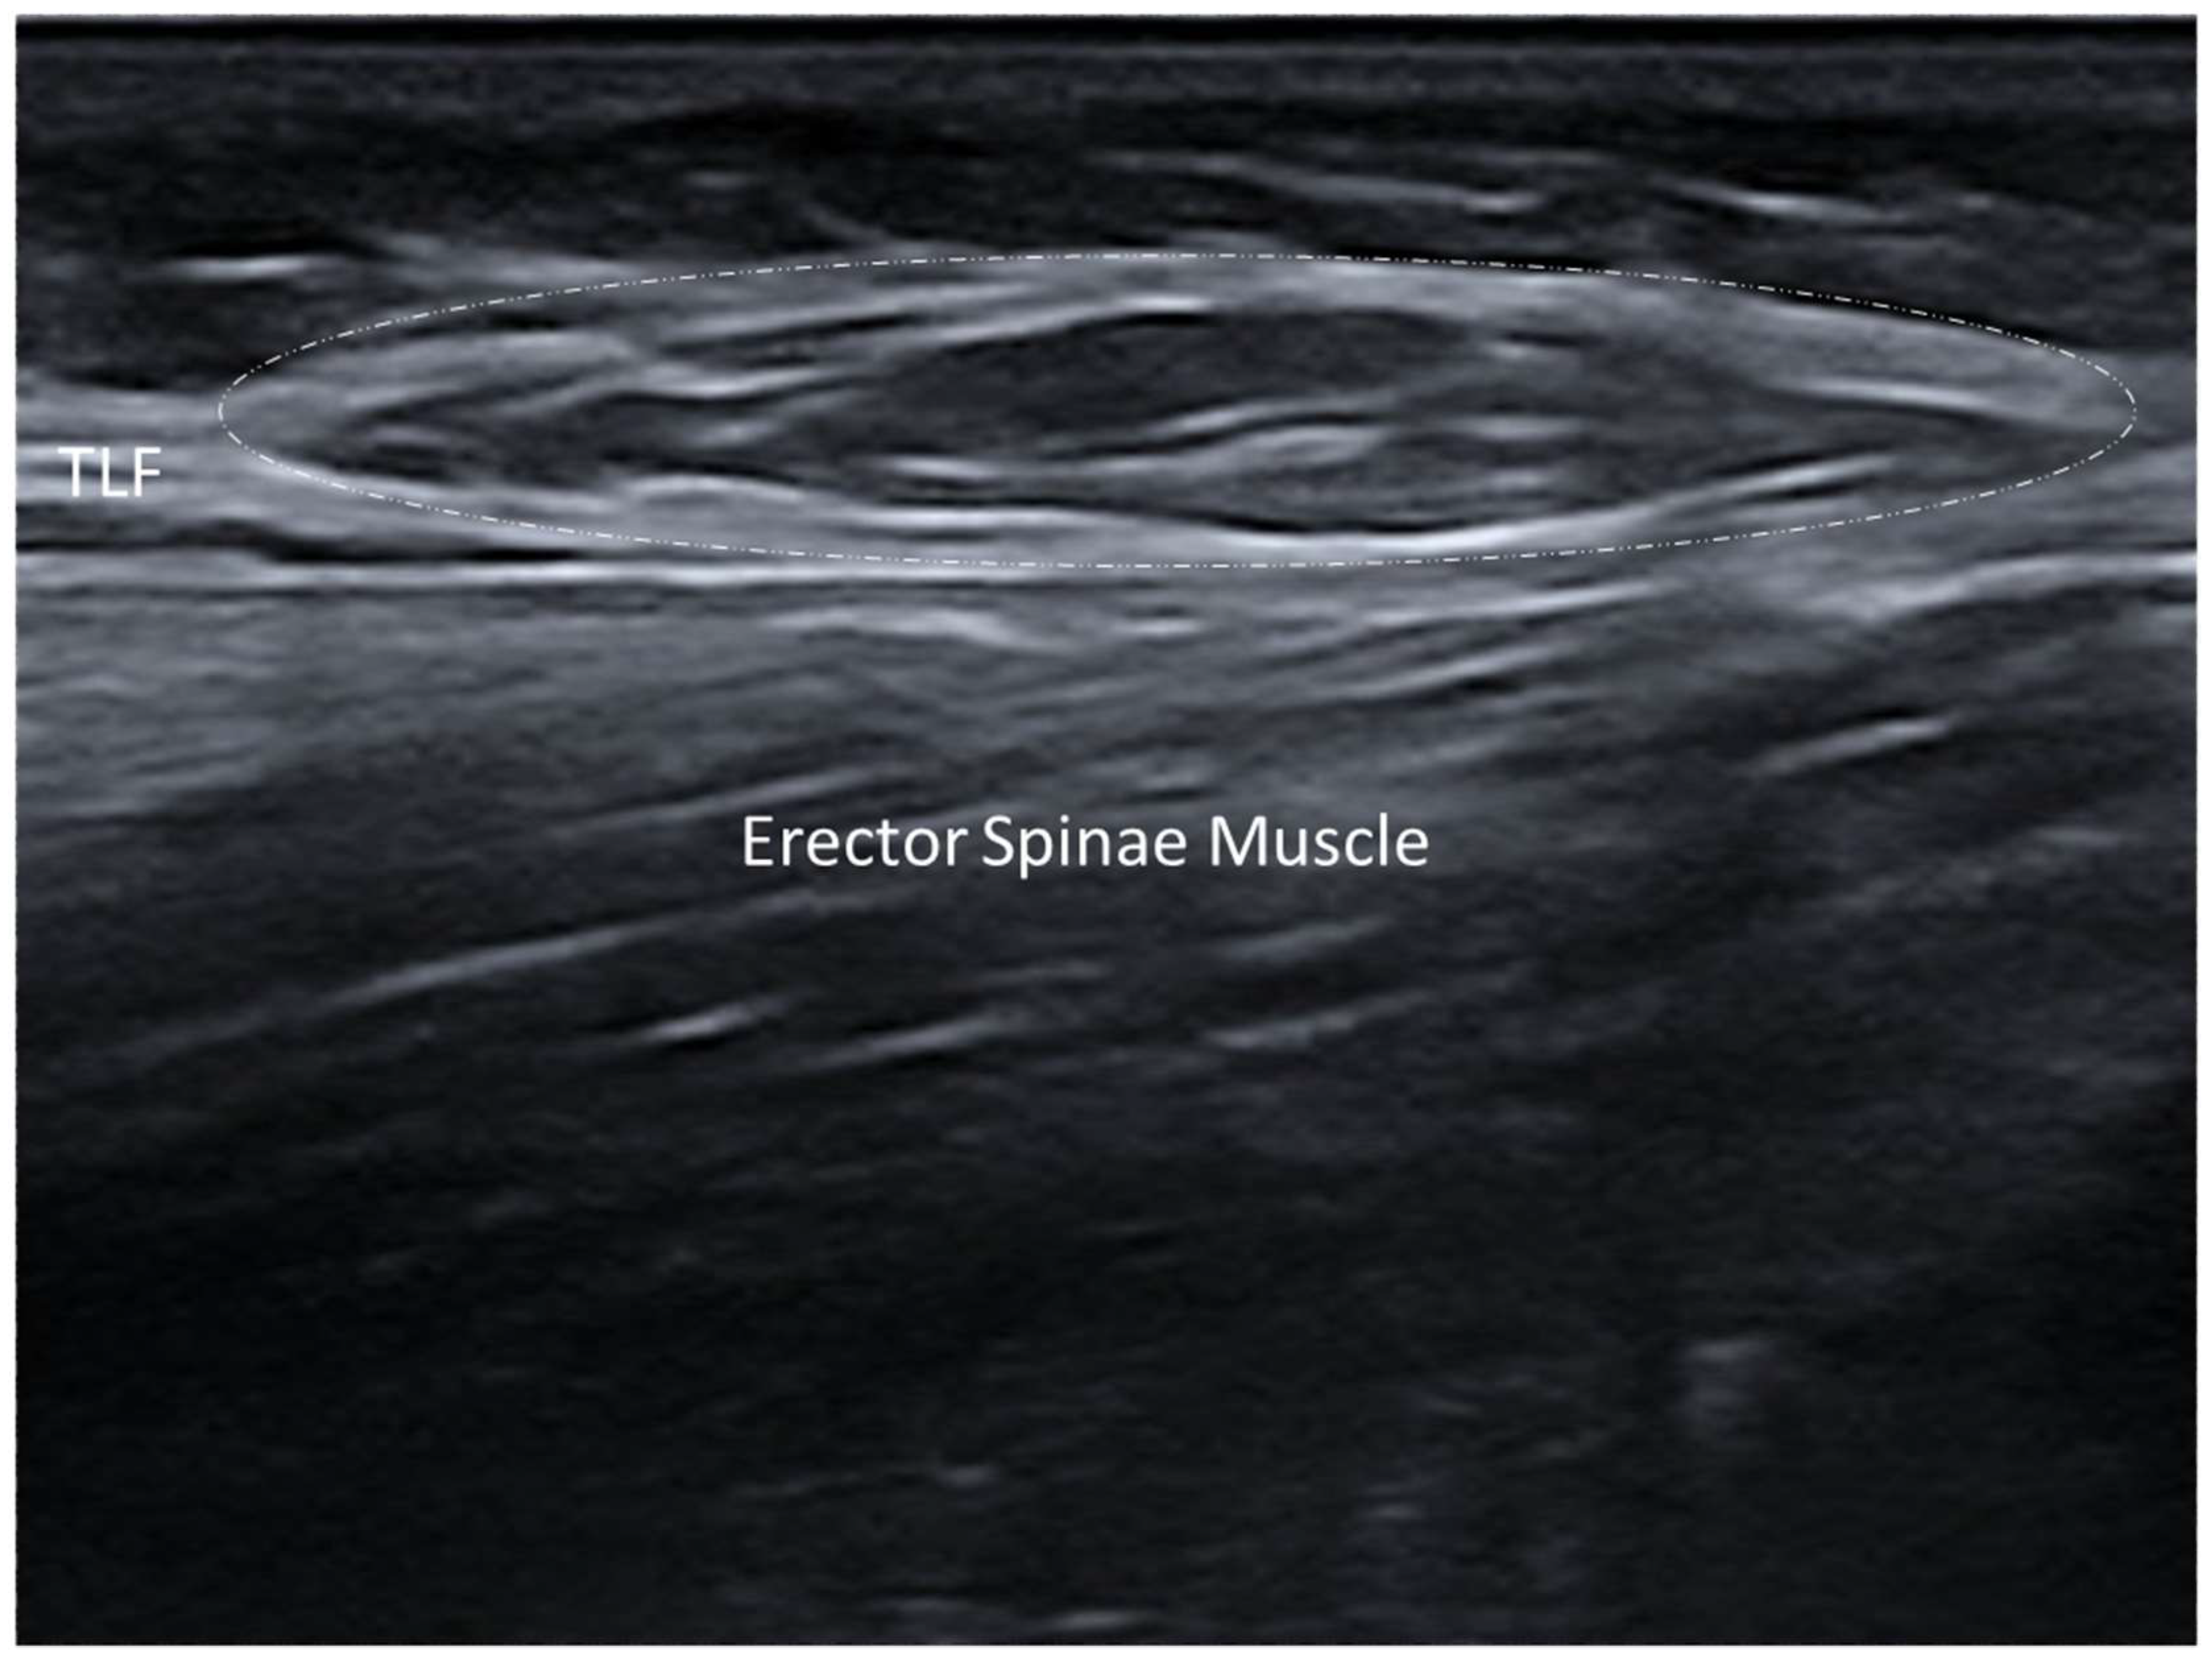

- Pirri, C.; Pirri, N.; Guidolin, D.; Macchi, V.; Porzionato, A.; De Caro, R.; Stecco, C. Ultrasound Imaging of Thoracolumbar Fascia Thickness: Chronic Non-Specific Lower Back Pain versus Healthy Subjects; A Sign of a “Frozen Back”? Diagnostics 2023, 13, 1436. [Google Scholar] [CrossRef] [PubMed] [PubMed Central]

3.2.2. Densification